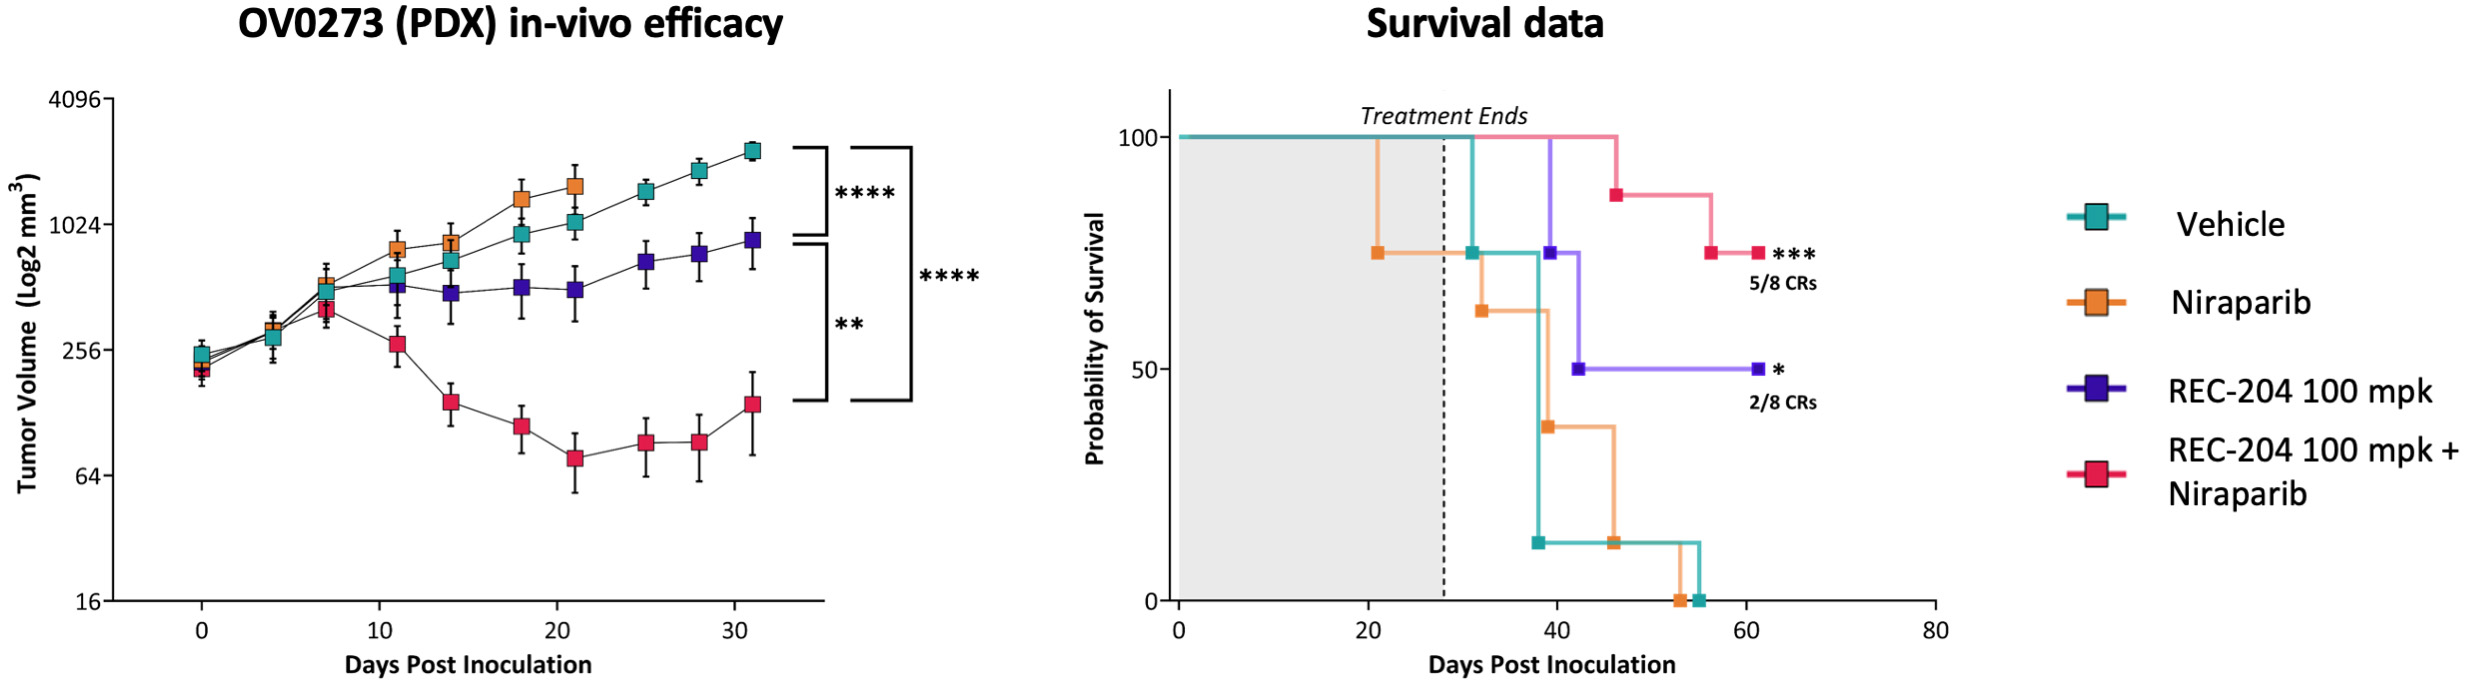

•Advanced our RBM39 program in homologous recombination proficient ovarian cancer and other solid tumors to IND-enabling studies